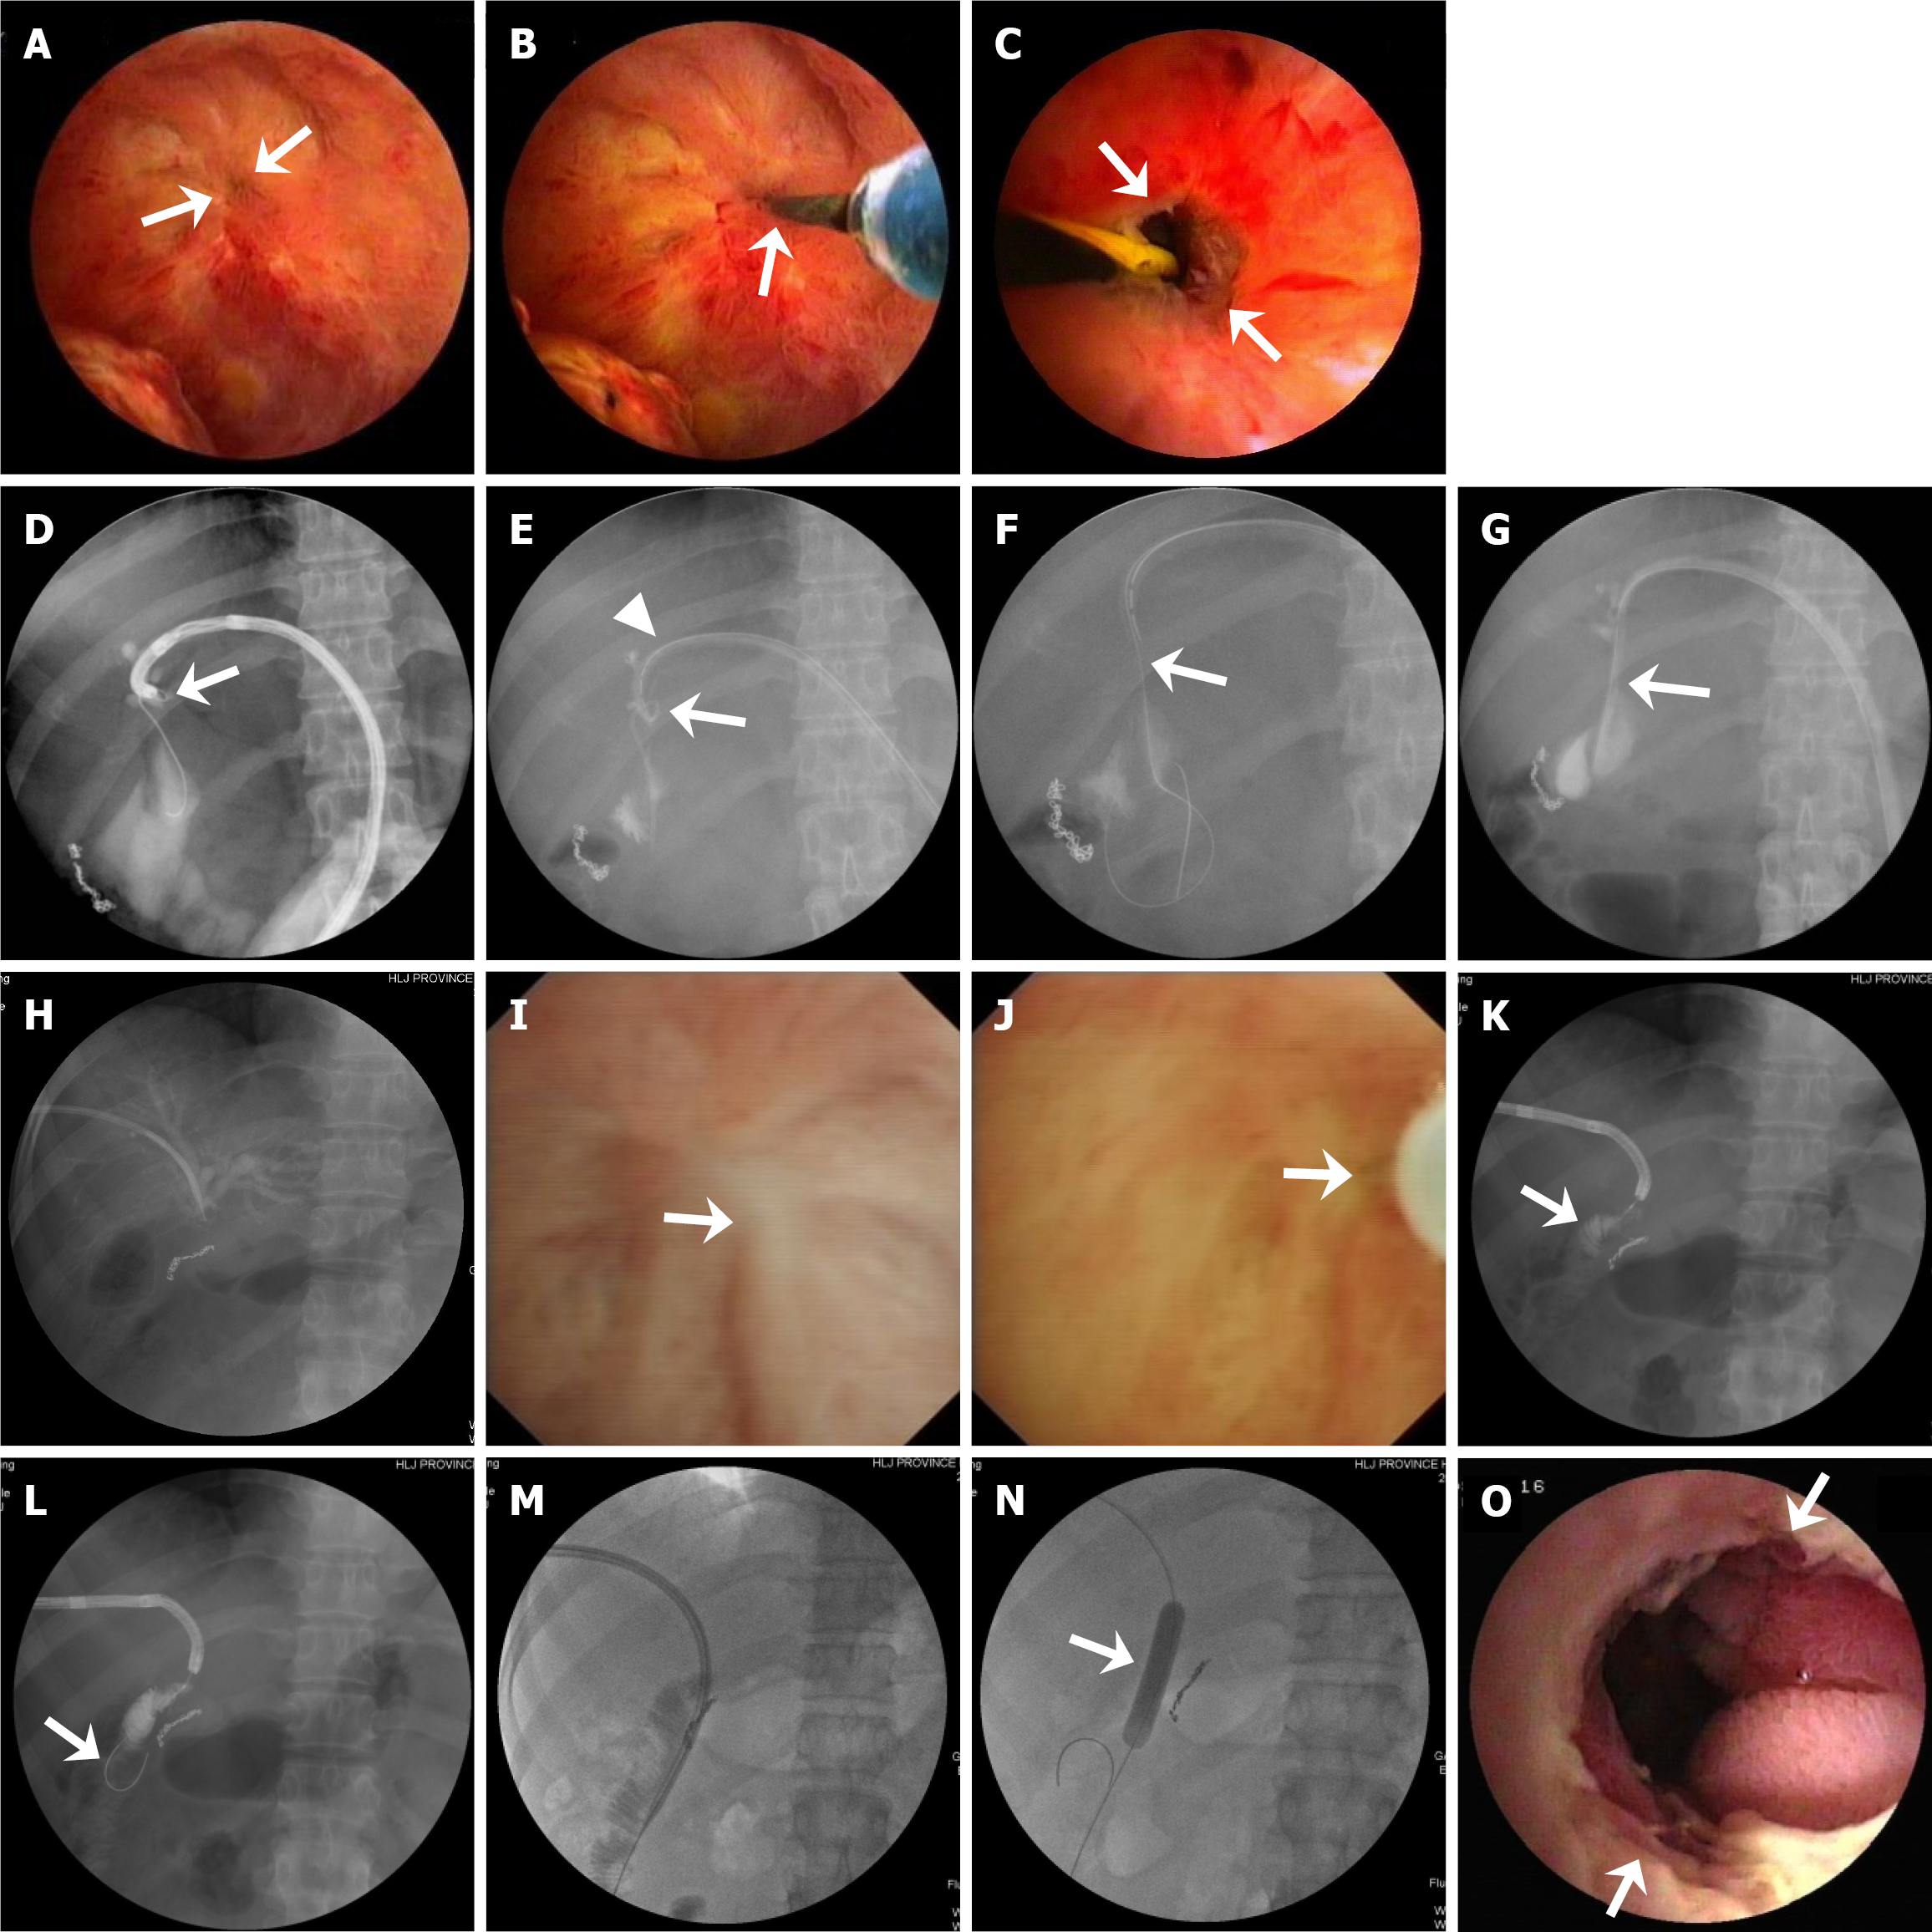

PTCS-assisted stricture dilation, anastomotic recanalization, and biliary stone therapy were performed in 31, 8, and 36 patients, respectively (Figure 1). Specifically, of the 40 patients, 31 patients (including 2 with mild, 11 with moderate, and 18 with severe anastomotic strictures) received BD (n = 27) (Figure 2A-C) or bougie dilation (n = 4). Nine patients did not receive stricture dilation due to complete anastomotic occlusion with failed anastomotic recanalization (n = 1) or mild strictures (n = 8). The eight patients with complex strictures achieved successful BD through PTCS-assisted guidewire passage beyond the stricture (Figure 2D). Among the 19 patients with a severe stricture, 11 patients received stricture dilation without pre-recanalization, and 8 patients received PTCS-assisted recanalization with a guidewire (n = 4, Figure 3A-C), microcatheter and microguidewire system (n = 2, Figure 3D-G), or a needle knife (n = 2, Figure 3H-O). The recanalization procedure was successful in seven (87.5%) of these patients who subsequently received stricture dilation by a balloon dilator (Supplementary Figure 1A and B) or a plastic bougie (Figure 3D-G). Of the 36 patients with biliary stones (9 and 27 with extrahepatic stones and intrahepatic stones, respectively), 20 and 16 patients received EHL/LL and stone removal with basket, respectively (Figure 4A-D).

PTCS-assisted biliary stone fragmentation/removal was successful in 34 (94.4%) of the 36 patients with biliary stones (Figure 4 and Table 3). Particularly, technical success was achieved in 25 (92.6%) of the 27 patients with intrahepatic stones, including 11 (40.7%) and 16 (59.3%) with monolateral and bilateral stones, respectively (Supplementary Table 1); the successful PTCS-assisted stone removal procedures in a case with intrahepatic stones including a large stone (1.4 cm × 1.9 cm) in the right posterior upper branch duct are illustrated in Figure 4E-L.

It has been recommended that a microcatheter, thin bougie, or special dilation device be applied when a balloon dilator cannot pass through a severe stricture[7,26,27]. In the present study, PTCS-assisted recanalization was successful with a guidewire in four patients whose anastomosis was as small as a pinhole, a dimple, or even hard to locate; a microcatheter system in two patients with strictures of sharp angulation and/or a looping configuration; or a needle knife in one of two patients with scars converging the mucous membrane at the stricture with an invisible anastomotic orifice. Since 2014, we have used the microcatheter system with a 5-Fr microcatheter (made ≤ 3 Fr at the tip) and a stiff 0.025-inch guidewire in patients with PTCS therapy. We assumed that the microcatheter would reduce the resistance of the catheter to pass through the stricture due to its small caliber and the very small space between the lumen of the catheter tip and the guidewire, allowing it to pass through the stricture. We designed a microcatheter (75 cm in length) that was used to dilate the stricture and also guide the indwelling PTCS catheter to connect with the bile bag and maintain PTCS access. Our experience is that when the microcatheter is left in the stenotic place for 1-2 weeks, the stricture becomes relaxed, further enabling the thin bougie to pass through and eventually dilate the stricture. Additionally, our technique for PTCS-assisted recanalization with a needle knife is different from the previously reported by Lim et al[18]. Since fistulotomy with a needle knife is a blind technique and associated with a risk of biliary perforation or bleeding, we punctured a 25-gauge injection needle into the center of the scar under direct visualization (Figure 3J) and injected the contrast medium in two patients. After the jejunal circular fold was visualized by radiography under fluoroscopy, a needle-knife pa

At present, BBAS is mainly treated with BD of anastomotic stenosis, through enteroscopy-assisted ERCP or PTBD[4,6,7], and bile duct stones are mainly cleared by PTCS[3]. However, there are few reports on the treatment of BBAS concomitant with bile duct stones[11]. It is difficult to clear intrahepatic stones with ERCP, especially those in the B6, B7, and B3 segments of the bile duct. In a recent European multicenter study[8], a thin (10.8 F) and short (65-cm) device (i.e., SpyGlass Discover) was used for PTCS to diagnose and treat biliary diseases. SpyGlass-guided EHL with a median of one session achieved a clinical success rate of 96.6% for the treatment of bile duct stones in 29 patients, of whom only 14.7% had intrahepatic stones, which were more difficult to clear[8]. However, this study did not explore the treatment of anastomotic strictures. Recently, a Japanese study compared DBE with PTBD for the treatment of hepatolithiasis after hepaticojejunostomy[28]. It was reported that of the 84 patients eligible for DBE, the hepaticojejunostomy site was reached in 42 (87.5%) patients. The complete stone removal rate of 85.7% (36/42) was achieved with DBE in patients with a median stone diameter of 8 mm (interquartile range: 6-10 mm), with 29 (69.0%) patients being treated with mechanical lithotripsy, whereas the rate was 90.2% (37/41) with PTBD in those with a stone diameter of 7 mm (interquartile range: 7-10 mm), with 31 (75.6%) patients being treated with PTCS-assisted EHL[28]. These results revealed that the success rate for stone therapy is not very high with DBE and PTBD, even for small stones (all ≤ 10 mm). In the present study, we observed that PTCS-assisted stone therapy achieved technical success (i.e., complete stone removal) in 94.4% of cases. Notably, 50.0% and 22.2% of the stones were between 10 mm and 20 mm and > 20 mm, respectively, and the technical success rate was 88.9% for these large stones. Moreover, 75.0% of the stones were located in the IHD, and technical success was achieved in 92.6% of these cases. Our findings indicate that PTCS-assisted stone therapy has advantages, especially for large stones by PTCS-EHL or PTCS-LL lithotripsy, or multiple intrahepatic stones, since the cholangioscope has accessibility to any location of biliary tree dilation. In the present study, one patient with a complex stricture had bilateral intrahepatic stones, including a large stone in the right posterior upper branch duct. Because of the presence of variations in the right anterior and right posterior sectoral ducts (segments 6 and 7)[29] in this patient, PTCS initially failed to observe the stenotic bile duct opening, and cholangiography also failed to show the right posterior branch duct and stones. However, both abdominal ultrasound and CT showed a large stone in the duct (segment 7). Under the guidance of PTCS, a guidewire entered the right posterior branch bile duct, and cholangiography with an ERCP cannula clearly showed the large stone in the right posterior upper branch duct. PTCS-assisted stricture dilation procedures (i.e., BD and the placement of an indwelling PTCS catheter in the branch) were performed, and the stricture was relaxed one week later. Then, a cholangioscope was sharply looped and inserted into the right posterior upper branch duct, showing that the blocky stones had been ground into multiple pieces by the indwelling PTCS catheter. Finally, the stones were successfully removed by further using a basket mechanical lithotripsy and washed out of the duct (Figure 4E-L).